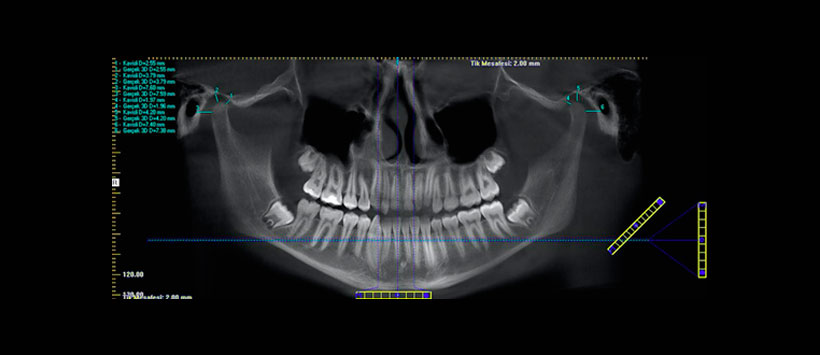

Se analizaron las imágenes de CBCT de 60 pacientes (edad de 18 a 37 años) y se evaluaron retrospectivamente. Los pacientes fueron divididos de acuerdo a sus maloclusiones (clases I, II y III). El condilo a la eminencia, el condile-tofossa, y las distancias de cóndilo a meato se midieron digitalmente con el software i-CAT. (Figura 1 y Figura 2) Obteniendo como resultado que las distancias de cóndilo a fosa izquierda y derecha fueron los parámetros más variables entre las clases analizadas. Las distancias de cóndilo a eminencia y de cóndilo derecho a fosa fueron significativamente diferentes entre las clases. Los pacientes masculinos parecían tener una mayor distancia de cóndilo a fosa en el lado derecho en los grupos de Clase I y III. La distancia media de condilo a eminencia, de condilo a fosa y de condilo a meato en el lado derecho fue el mejor en la clase II. Como conclusión entre los tres tipos de maloclusión (clases de ángulo I, II y III), los cóndilos en los lados derecho e izquierdo no eran exactamente simétricos o localizados centralmente dentro de la fosa glenoidea.